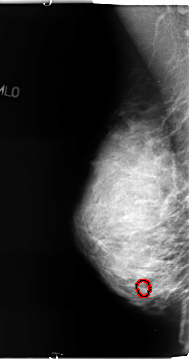

B_3127_1.LEFT_MLO

LEFT_MLO LINES 4696 PIXELS_PER_LINE 2376 BITS_PER_PIXEL 12 RESOLUTION 50 NON_OVERLAY